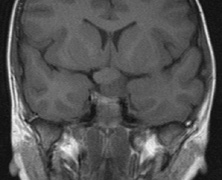

2. Subependymal nodules (SEN) are typically found along the lateral borders of the ventricles and parehncymal brain lesion (“cortical tubers”) (Figs. 14 and 15). Calcification in the first year of life is rare.132

Fig. 14. Tuberous Sclerosis Complex: Sub-Ependymal nodules. These are typically found along the lateral borders of the ventricles.132

Fig. 15. Tuberous Sclerosis Complex. (a) Patient 1: Axial CT scans demonstrating typical calcification of subependymal nodules in a 13-year-old girl with a history of seizures. (b and c) Patient 2. (b) Axial T2-weighted images demonstrate calcified subependymal nodules (arrowheads) and cortical tubers typical of tuberous sclerosis. (c) Widespread cortical tubers are seen on a coronal FLAIR sequence as thickening of the cortex and high signal of the subcortical white matter.